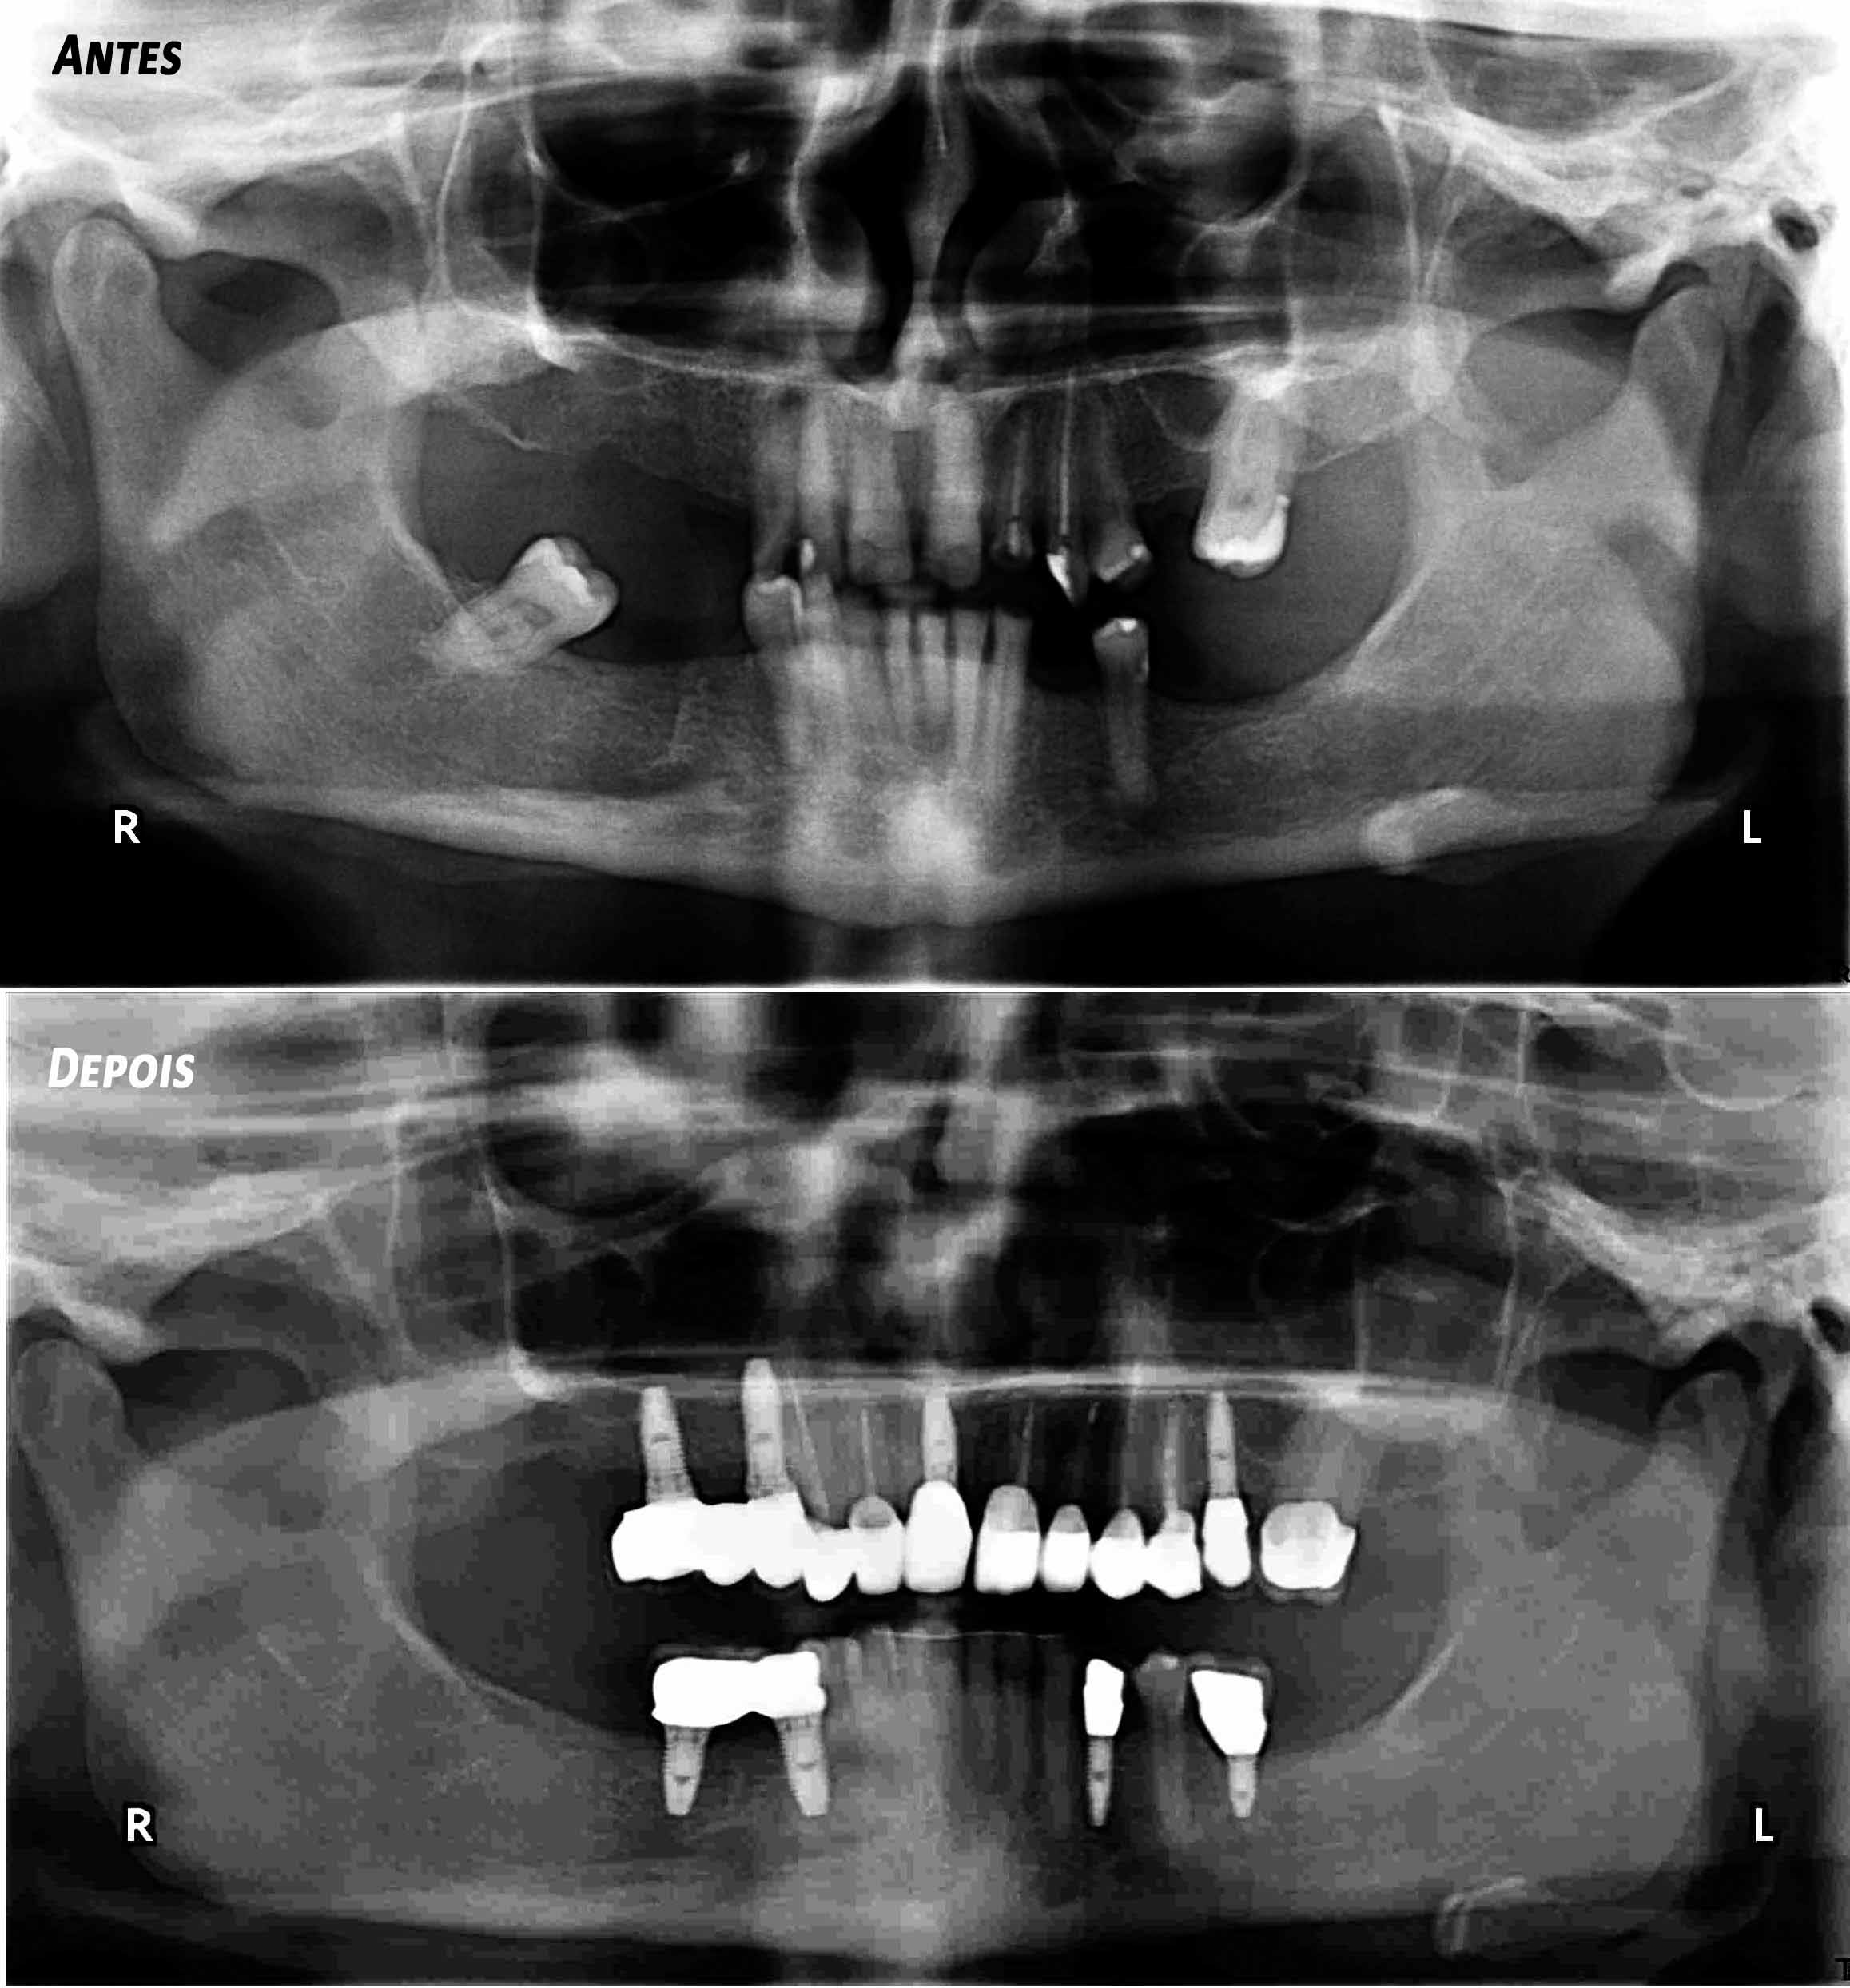

Paciente com limitações funcionais e estéticas graves

Reabilitação Complexa - Tratamento

Mantiveram-se os dentes naturais remanescentes que tinham bom prognóstico e com Aparelho Ortodôntico fixo foram corrigidas as suas posições.

Posteriormente foi feita cirurgia para colocação de alguns Implantes.

Finalizou-se com colocação de Coroas Cerâmicas.